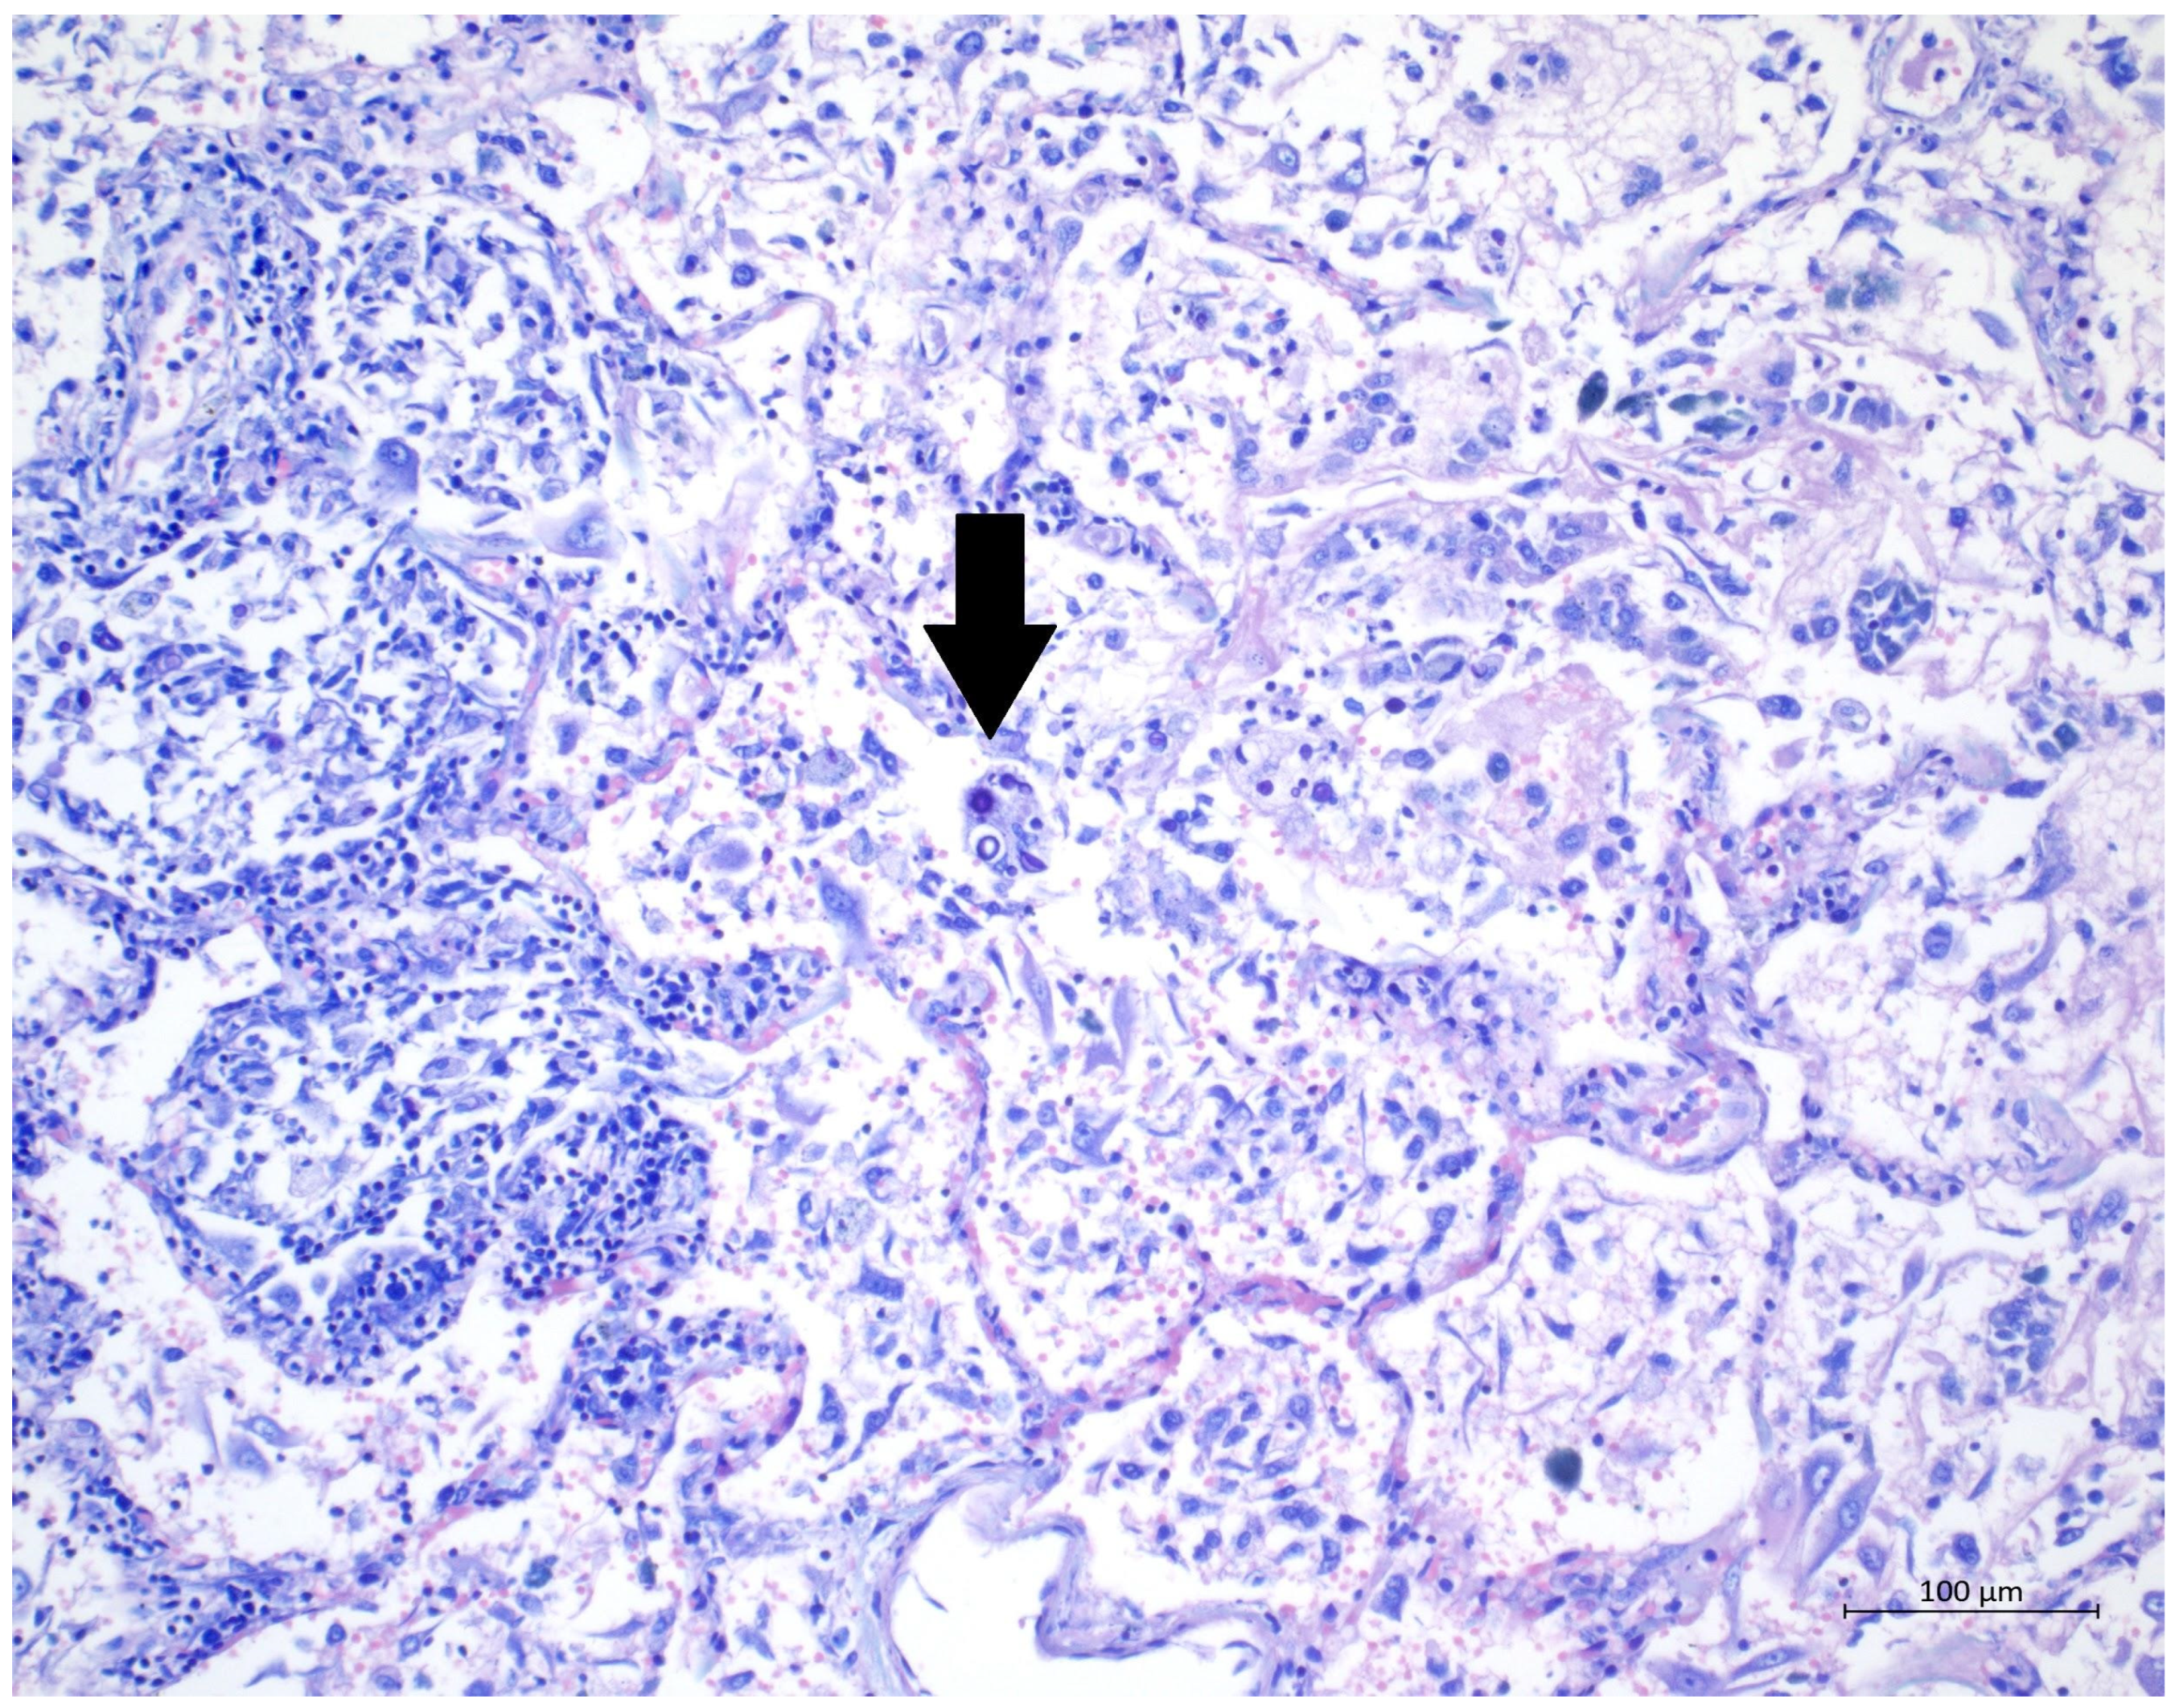

Figure 3.

(H&E, 40×) High magnification of H&E staining, presenting alveolus with DAD-related changes; several oval to round yeasts with capsules suggestive of cryptococci are clearly visible.

A 60 year old male smoker with a history of arterial hypertension and myocardial infarction developed typical COVID-19 symptoms in April 2021—cough, exertional dyspnoea, chest tightness, and fever. Developing prior to the widespread availability of antiCOVID-19 vaccines, he was unvaccinated. Four days after the onset of symptoms, he was admitted to the Pulmonary Department of the University Hospital Brno due to the worsening dyspnoea. He tested positive for SARS-CoV-2. The exact viral variant was not identified. The predominant variant in the Czech population was B.1.1.7 (Alpha) at that time. His initial chest X-ray revealed diffuse lung infiltrates, especially in the right upper-middle quadrant. Despite receiving standard treatment with remdesivir for five days, corticosteroids (methylprednisolone 80 mg intravenously per day), and a prophylactic dose of low-molecular-weight heparin (LMWH), his dyspnoea worsened. Hence, supplemental oxygen and antibiotics (i.e., clarithromycin 500 mg IV BID and ceftriaxone 2 g IV BID for 5 days) were administered. Due to the progressively increasing levels of D-Dimers in laboratory tests, CT angiography was performed, showing typical findings consistent with COVID-19 pneumonia of diffuse lung parenchyma involvement without any signs of pulmonary embolism (Figure 1). The patient’s oxygen was gradually increased to achieve a peripheral blood saturation of >90%. On day 11, the patient was transferred to the ICU after his saturation dropped to 50–60% despite an oxygen flow via face mask of approximately 15 litres per minute. High-flow oxygen therapy (HFOT) with awake prone positioning was commenced, and corticosteroids were switched from methylprednisolone 80 mg to dexamethasone 6 mg IV per day. Despite ten days of corticosteroid administration, the patient’s clinical condition began to deteriorate significantly, and his hypoxaemia worsened. On day 12, he was intubated and placed on invasive ventilation with aggressive parameters (positive end-expiratory pressure: 12 cm H2O; fraction of oxygen: 80%). Bronchoalveolar lavage (BAL) was performed with the PCR testing showing more than 2 million copies of SARS-CoV-2 per millilitre (a significant number); no fungal DNA was detected at this time. As the patient became anuric, daily dialysis treatment commenced on day 13. Ventilator-associated pneumonia (VAP) caused by Klebsiella pneumoniae producing extended-spectrum beta-lactamase (ESBL) was confirmed by BAL fluid cultivation, and meropenem 2 g per day in continuous infusion was started. Serum levels of cardiac markers were elevated (troponin T: 67 ng/L; NT pro Brain Natriuretic Peptide (NTproBNP): 3892 ng/L), indicating advancing myocardial injury. Norepinephrine infusion was needed to achieve adequate blood pressure. The capillary refill time was prolonged over 2 s, consistent with circulatory dysfunction. A day later, the patient developed atrial fibrillation and hemodynamic instability with doses of norepinephrine up to 0.5 µg/kg/min. On day 16, a tracheostomy was performed, while the ventilation remained fully controlled with a P/F (PaO2/inspiration fraction of O2) index below 150. Two days later, the progression of circulatory dysfunction became apparent, accompanied by an elevation of inflammatory markers. Follow-up BAL was performed, empirical vancomycin was added on day 19, and doses were adjusted respecting dialysis procedures. Abdominal ultrasound revealed no clear site of a new infection. Blood cultures were negative, and BAL showed more than 3 million copies of SARS-CoV-2 and 1200 copies of Cryptococcus neoformans per millilitre/BAL. Serum panfungal antigen ((1,3)-β-glucan D) and serum cryptococcal antigen (i.e., glucuronoxylomannan) levels were negative. Over the next four days, organ dysfunction slightly improved; therefore, the patient was slowly weaned-off sedation, and the mode of ventilation was switched to pressure support. On day 21, vancomycin was switched to linezolid 600 mg IV BID. On day 22, a follow-up BAL was performed. PCR showed borderline positivity for Cryptococcus neoformans (300 copies per millilitre), and serum positivity for cryptococcal antigen was detected. Combined antifungal therapy with liposomal amphotericin B (Abelcet) 500 mg IV per day and fluconazole 800 mg IV per day was commenced. Blood cultures were negative for bacteria and fungi. Cerebrospinal fluid analysis, including PCR, ruled out CNS dissemination. On day 24, the patient’s circulatory instability progressed rapidly with no response to vasopressors and inotropes, which led to a subsequent cardiac arrest followed by unsuccessful cardiopulmonary resuscitation (CPR). Multiorgan dysfunction caused by COVID-19 infection and cryptococcal pneumonia was stated as the primary cause of death from a clinician’s perspective. The most significant feature during the histopathological examination was the severe diffuse alveolar damage (DAD) (Figure 2), specifically its exudative/proliferative stage, due to the prolonged period of COVID-19 pneumonia. In addition, a considerable number of dispersed intra-alveolar microorganisms, with a thick mucus capsule, were found in the lung parenchyma (Figure 3). These microorganisms (variably sized: approximately 7–20 μm) stained with both Alcian blue (Figure 4) and Giemsa (Figure 5). There was only a very subtle inflammatory reaction in the surrounding tissue, mostly lymphocytic. A post-mortem lung smear was microbiologically tested and returned positive for Cryptococcus neoformans. Thus, we consider secondary lung cryptococcosis as proven. Respiratory failure as a result of DAD was the immediate cause of death of the patient.